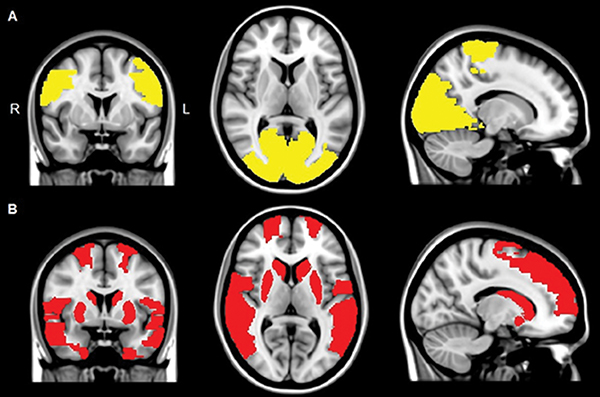

The results showed that in all the patients with Parkinson’s disease, multiple brain areas communicated less with the rest of the brain as compared to the control group. However, in patients experiencing visual hallucinations, several additional brain areas showed this decreased connectivity with the rest of the brain — especially in areas that are important in maintaining attention and processing of visual information. The study authors suggest that this disconnection of these brain areas may contribute to the generation of visual hallucinations in patients with Parkinson’s disease.

“We found that the areas in the brain involved in attention and visual processing were less connected to the rest of the brain,” said study author Menno M. Schoonheim, PhD, from the Department of Anatomy and Neurosciences at VUMC. “This suggests that disconnection of these brain areas may contribute to the generation of visual hallucinations in patients with Parkinson’s disease.”